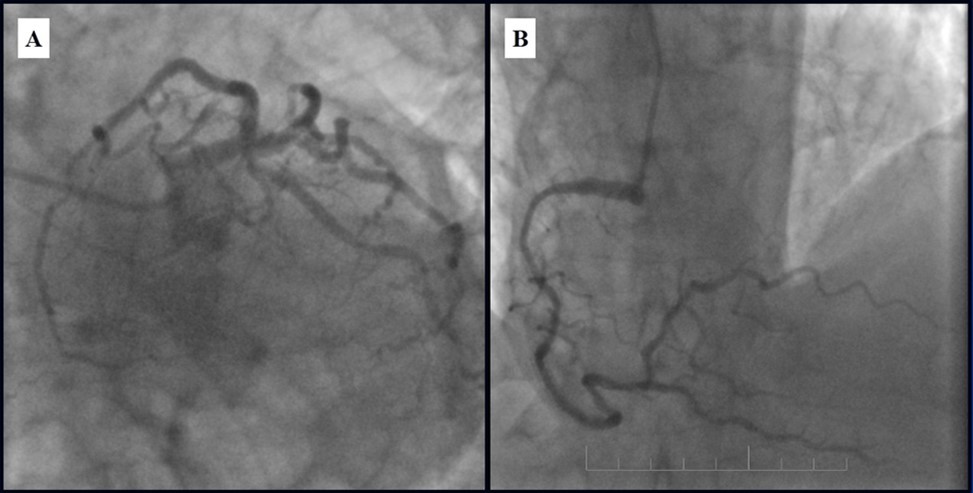

Subsequent coronary angiography eight months after the last PCI revealed patent stents with mild, non-significant restenosis in DES and 50-60% in-stent restenosis in BMS (Figure 13, Figure 14).

Figure 13.Subsequent CAG eight months after last PCI; A - Patent stents with mild, non-significant restenosis in left coronary artery; B - 50-60% in-stent restenosis in RCA.

Figure 14.Left coronary artery, follow-up CAG eight months after last PCI.